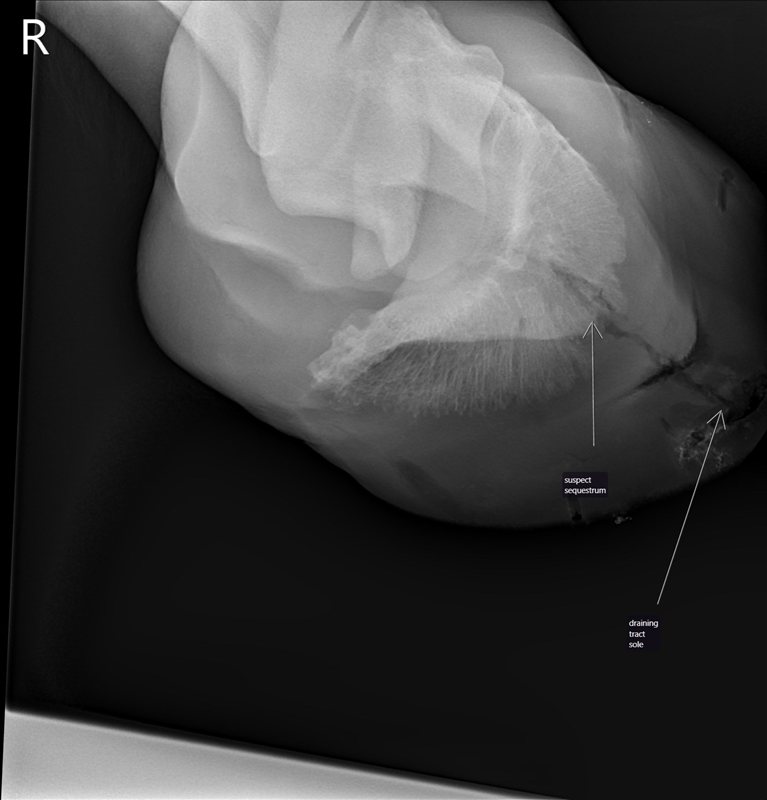

![]() |

| Pre-surgery x-ray with the vet’s labels. |